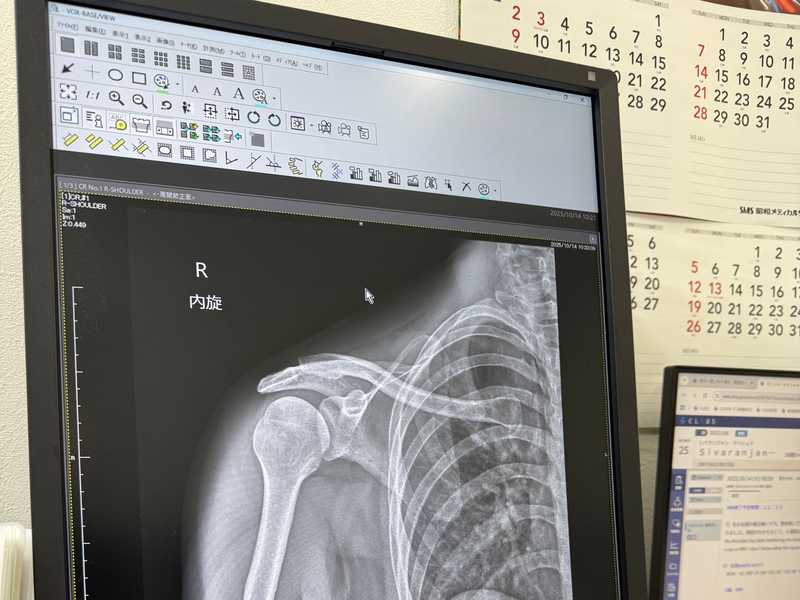

I went to the doctor and got an MRI. It turns out I have frozen shoulder. In Japan though they call it 50s shoulder since I guess 50 year olds typically get it… I am not in my 50s… ( ╯°□°)╯ ┻━━┻